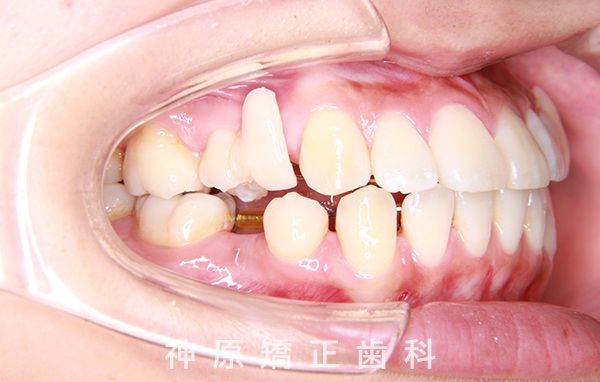

治療終了

治療前と治療後

今回の矯正治療にあたり、矯正精密検査の結果をもとに診断を行いました。その結果、左下の永久歯が生まれつき欠損していました。歯並びの乱れや口元の突出感を改善するため、小臼歯と残っている乳歯を抜くことが必要だと判断しました。